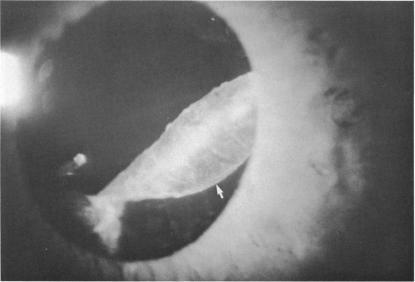

Exfoliation syndrome and occludable angles.

Trans Am Ophthalmol Soc. 1994;92:845-944.